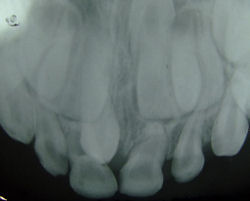

This slide is a cross section of a decalcified tooth.

Identify microscopically:

1. Pulp Chamber

2. Dentine

3. Cementum

4. Periodontium

5. Alveolar bone

Two supernumerary teeth at premaxilla

Cross section of a decalcified tooth

Very low magnification cross section of a decalcified tooth